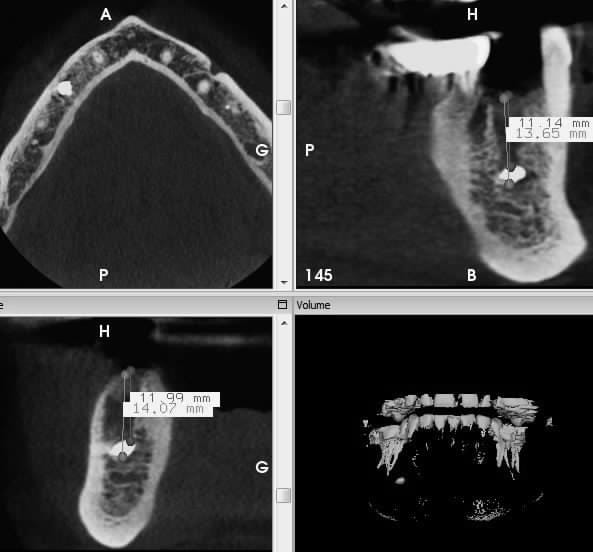

je dois poser un implant en place de 45 , il y a un residu de pate d'obturation à 11.14 mm de la crete . Deux option poser un implant de 10 mm au dessus ou descendre plus loin pour enlever le residu et poser un implant de 14 mm mais qui va se rapprocher dangeureusement du ndi (1.5mm) . Que feriez vous ?